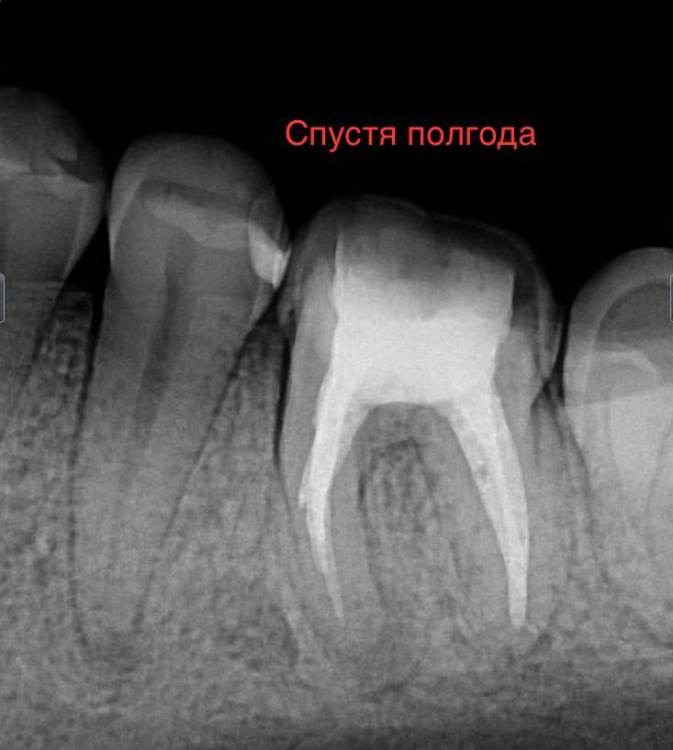

chacraborti Опубликовано 13 февраля, 2024 Поделиться Опубликовано 13 февраля, 2024 Делали ре-ендо зуба 36, прошел год прикрепляю снимок до и после. Прошло ли воспаление у верхушки корня? Ссылка на комментарий

kramer Опубликовано 13 февраля, 2024 Поделиться Опубликовано 13 февраля, 2024 Прошло 1 Ссылка на комментарий